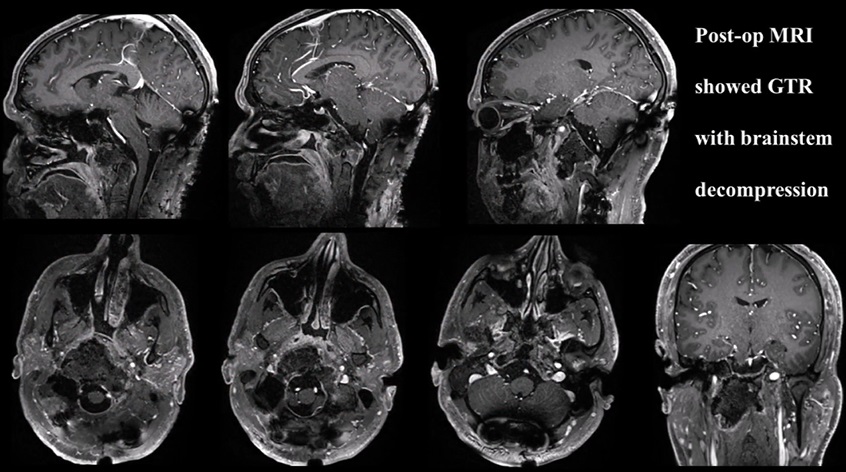

48岁男性较大脊索瘤复发,“双镜联合”成功手术

26岁男士较大颅颈交界区脊索瘤压迫脑干,福教授双镜联合全切巨型脊索瘤

53岁男性高难度岩斜区脑膜瘤